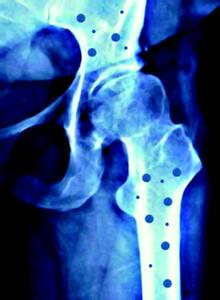

人體正常的骨代謝過程是骨組織不斷進行改建活動的一個複雜的過程,包括骨吸收和骨形成兩個方麵。該過程的順序一般認為是:激活——骨吸收——骨形成。首先,參與骨吸收的破骨細胞大量被激活,破骨細胞將骨基質溶解,並把骨中的鈣移出,形成骨吸收;隨後在骨吸收的表麵排列成骨細胞,成骨細胞合成非礦化的骨基質,同時把鈣運至鈣化區;最後,鈣、磷結晶逐漸沉積在骨基質中,骨基質鈣化,形成骨組織。在骨的代謝過程中,每天都有一定量的骨組織被吸收,又有相當數量的骨組織合成,兩者保持著動態的平衡。當骨吸收大於骨質形成,可出現骨丟失、發生骨質疏鬆症、骨軟化病等症。當骨形成而無相應的骨吸收時,則可出現骨質硬化。

骨的代謝過程受到體內許多因素的調節,鈣、磷、鎂、內分泌激素、維生素等多種因素均起著至關重要的作用。當這些因素的代謝發生異常時,就可造成骨代謝的紊亂。